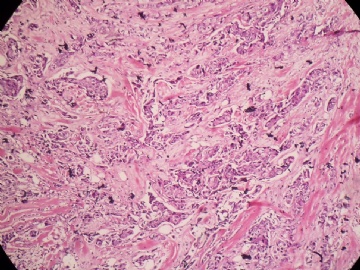

姓    名: ××× 性别:  女 年龄:  45

标本名称:  左侧近乳晕处肿物

简要病史:  患者描述有疼痛

肉眼检查:  肿物一个2.5*2*1厘米,切面灰白质地硬。

• 浸润性导管癌?图3

图3

上皮样细胞,大部分粘附成团成巢,明显浸润。大部分细胞大,核级别高,少数图中见松散的小细胞。未见原位癌。

大细胞考虑浸润性导管癌(3级),小细胞要排除小叶癌。如果有条件请做免疫组化。

Most likely it is INVASIVE DUCTAL CARCINOMA.

DO ER/PR/HER2 STAINS

应该是浸润性导管癌,标本可能有部分自溶现象。